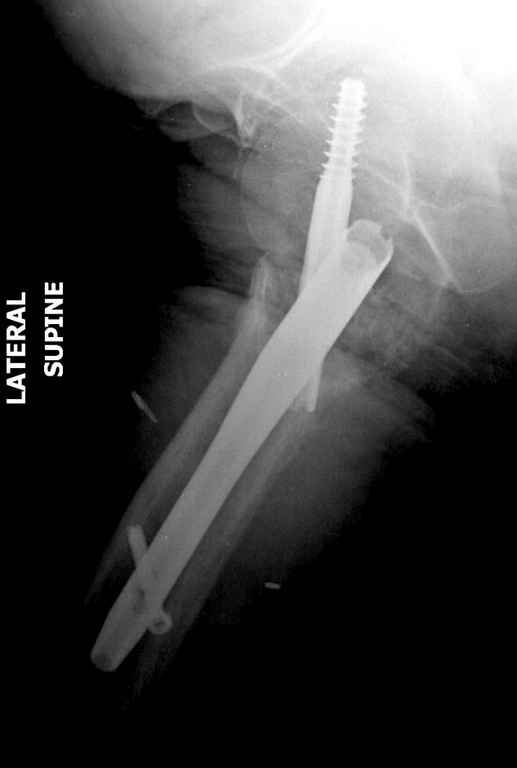

До выхода блокируемых гвоздей для фиксации косых подвертельных переломов в основном применяли Blade Plate. За счет уникальной конструкции создавался Fixed Angled Device, который соединял головку с диафизом, минуя зону перелома.

За счет особой конструкции клинка и подпорки (buttress) в диафиз создавалась стабильность, и предупреждалось скольжение по линии перелома. Перпендикулярная поверхность клинка предупреждала сгибательные и разгибательные смещения, и в сравнении с круглым винтом редко происходило прорезыванием.

Первые реконструкционные гвозди без блокировки винтов не смогли повторить преимущества, и из-за Z эффекта винтов происходило быстрое расшатывание.

С приходом менее агрессивных блокируемых цефаломедуллярных гвоздей (Gamma 3 и другие) изменилась тактика лечения. Несмотря на то, что вся стабильность держится вокруг одного блокирующего винта, в большинстве случаев гвозди приводили к успеху.

В данном случае в головке бедра и в вертлужной впадине огромный дефект, навряд ли удалением импланта или заменой на другой можно сохранить сустав.

Вашему вниманию представляется похожий случай, пациентке 70, осложнился в течение одного месяца после операции. Ревизия с заменой сустава, кабельная фиксация на трохантер. При установке в дистальном диафизе обнаружен тонкий кортикальный слой и сделана профилактика от возможного перелома аллографтом.